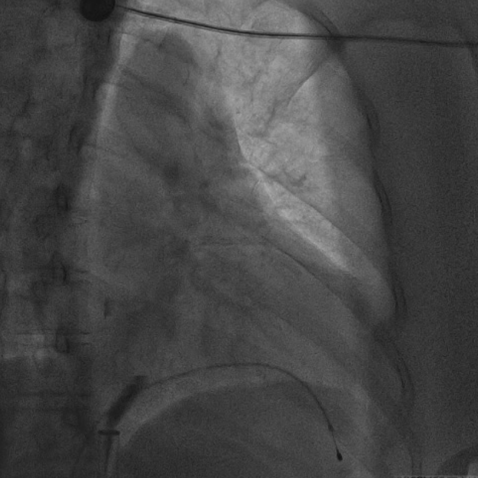

无导线起搏器被抓捕、拔除的术中影像

术前,汤宝鹏教授带领治疗团队对文献进行了详细查阅,对病情进行了充分而细致地评估,对术中可能出现的各种风险做好了各项应急预案。术中,手术团队使用圈套器成功抓捕无导线起搏器Micra尾端并顺利拔除,同时给患者植入左束支心脏再同步起搏除颤器。手术顺利,患者术后恢复良好。